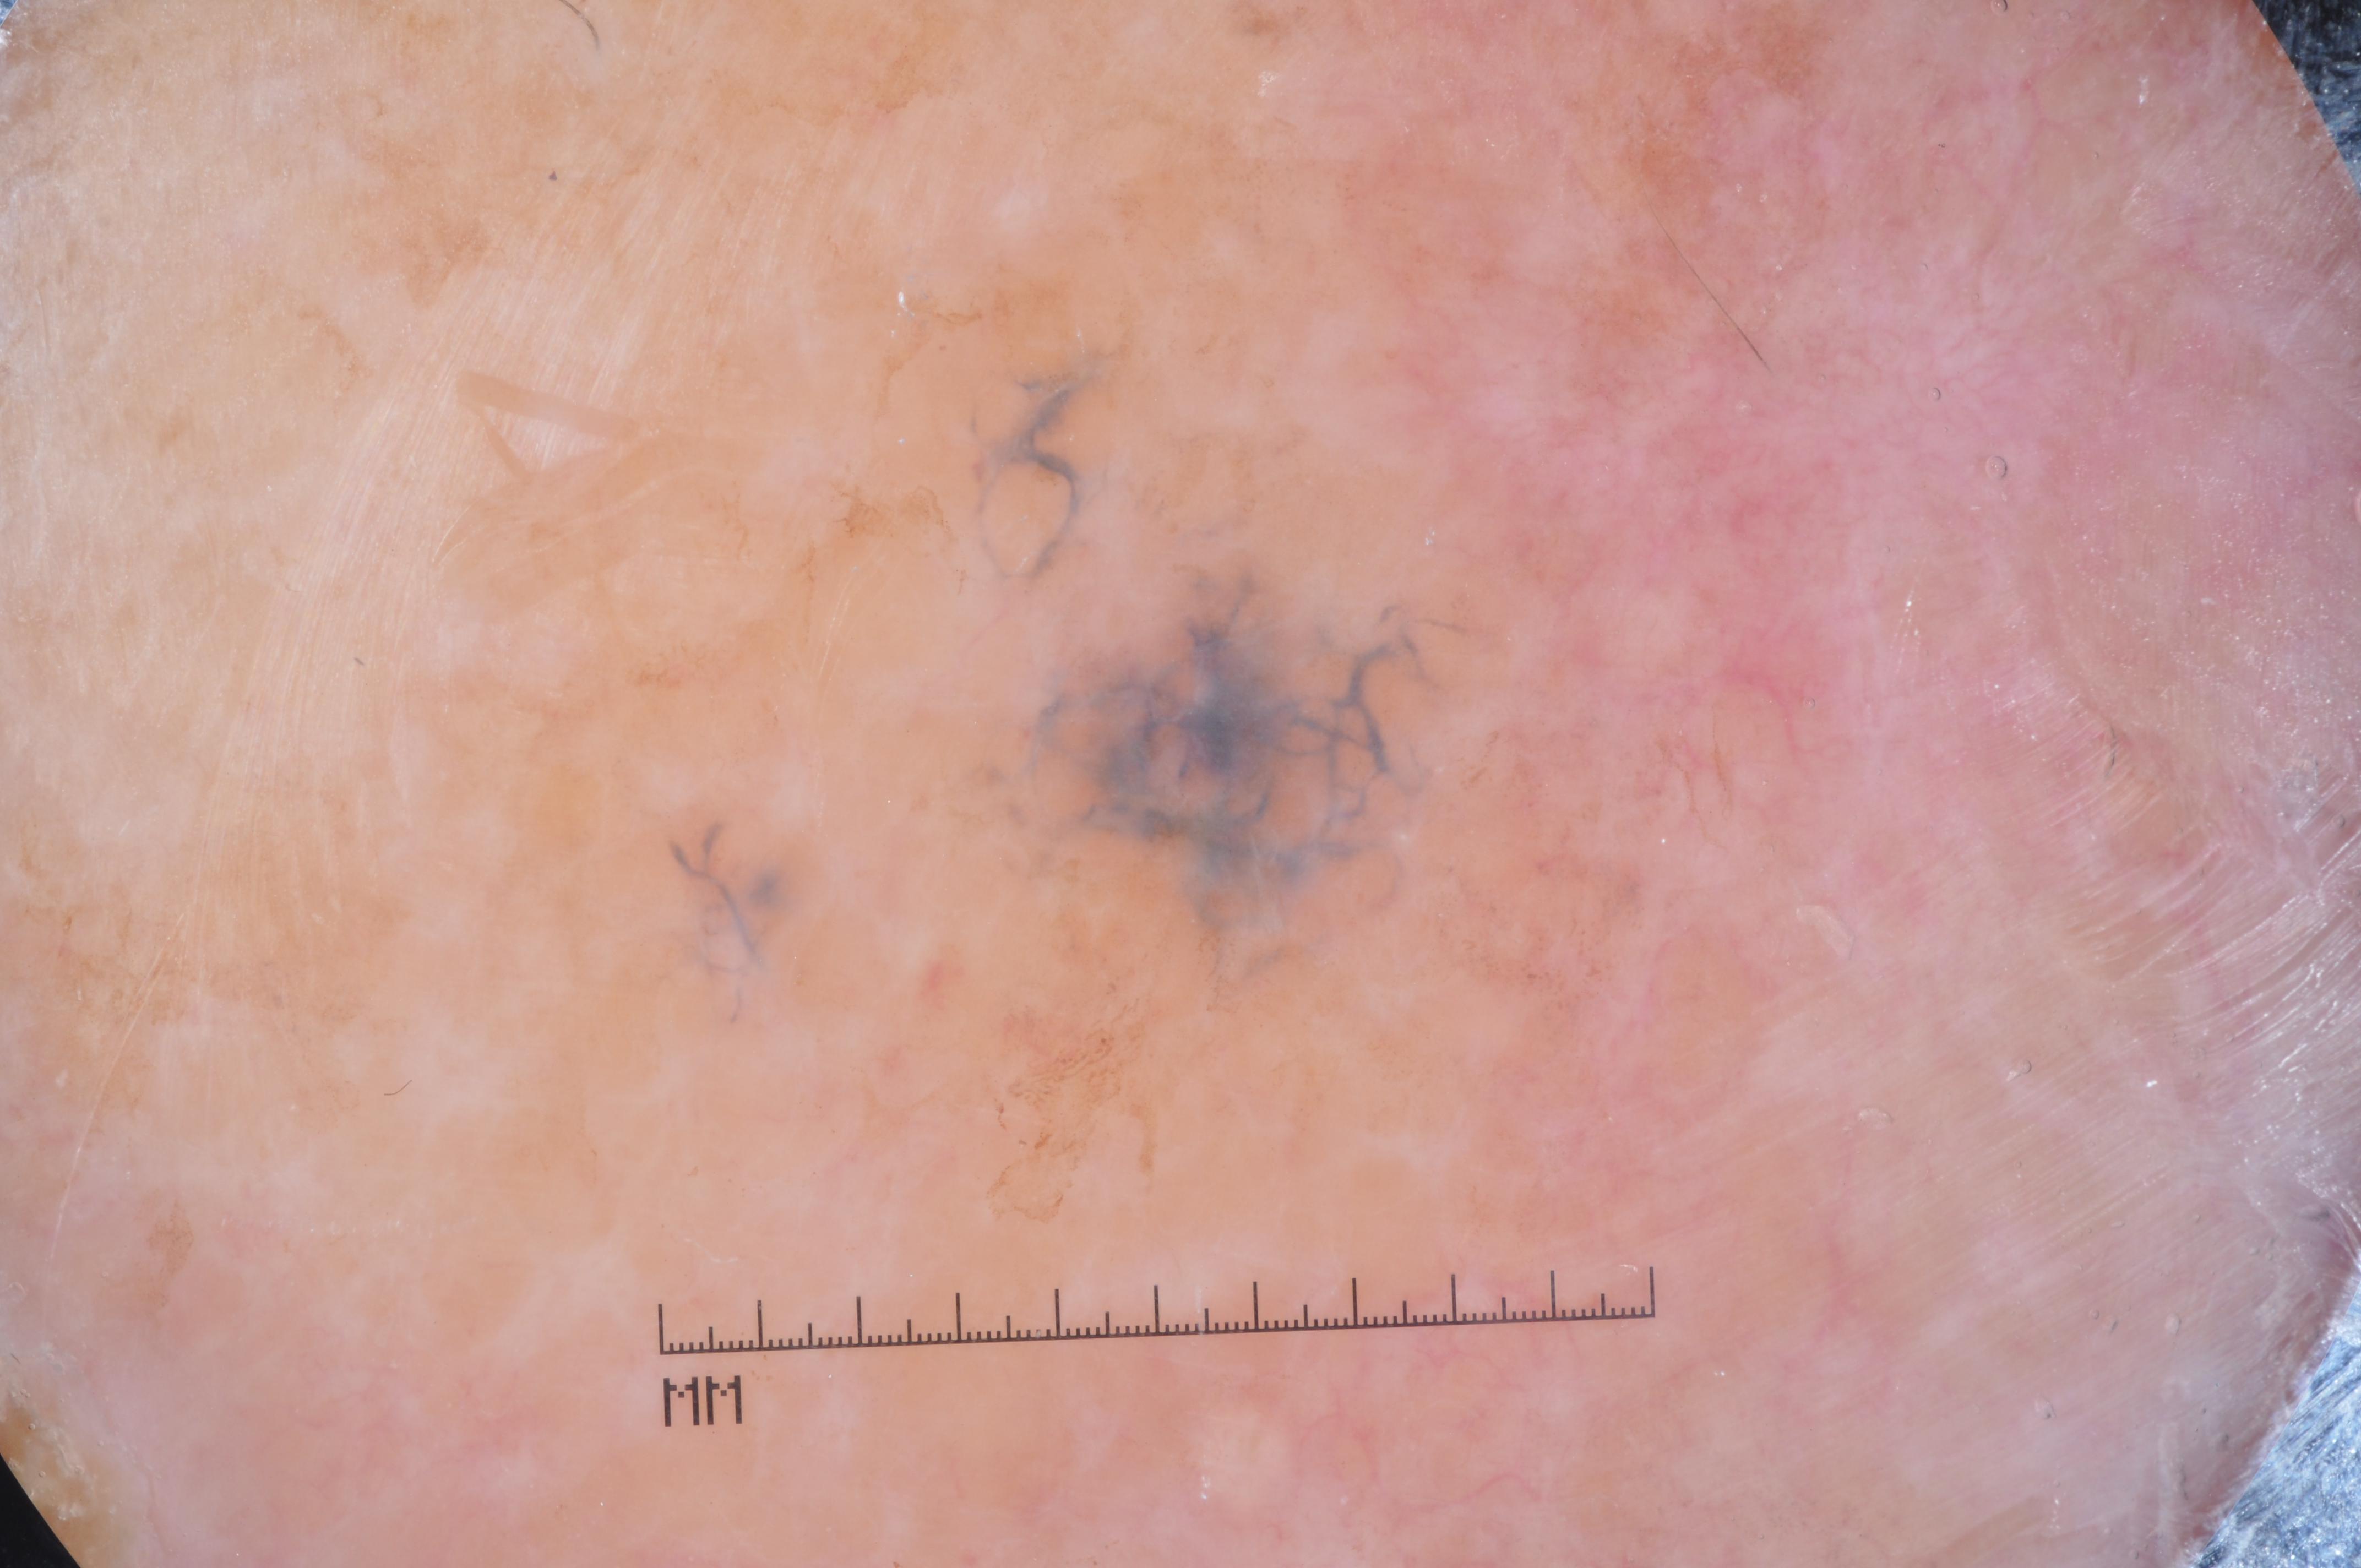

{

"age_approx": 65,

"anatom_site_general": "head/neck",

"concomitant_biopsy": true,

"diagnosis_1": "Malignant",

"diagnosis_2": "Malignant melanocytic proliferations (Melanoma)",

"diagnosis_3": "Melanoma metastasis",

"diagnosis_confirm_type": "histopathology",

"image_type": "dermoscopic",

"lesion_id": "IL_2152310",

"melanocytic": true,

"sex": "male"

}